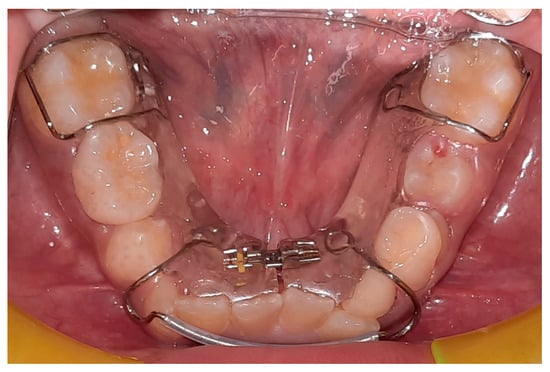

The lower jaw is considered the guiding arch in crowding therapy because it is difficult to modify its perimeter due to the more compact bone structure and the continuity with the mandibular branch, which does not allow for distalization [37,41]. In addition, the symphysis cartilage ossifies in the first year of life, so it is not possible to perform an orthopedic bone expansion, as in the upper jaw, working at the level of the median palatine suture [41,42]. The modalities of space recovery in mixed dentition are: arch perimeter increment, reduction in mesiodistal widths of teeth and serial extractions [2,43,44]. In the upper arch, the expansions are quite stable, but inferiorly, it is universally recognized that the expansion of the intercanine diameter always recurs, whereas expansion at the molar level is quite stable, which should be considered [27,45,46,47]. The space that can be recovered in the lower arch depends on the type of sector: in general, in the posterior sector, utilizing a lip bumper-style device, it is possible to recover a maximum of 2 mm of space per molar distalization in the posterior regions. At the molar level in the lateral sectors, the arch length could increase by about 0.4 mm; at the canine level, the arch length increases about 0.7 mm [48]. The vestibularization of one millimeter of the incisal margin in the anterior sector results in the gain of one millimeter of arch space, or roughly a ratio of one to one (changing the arch form) [47]. Schwarz’s appliance (Figure 3) and lip bumper (Figure 4) are two commonly used appliances for increasing lower dental arch dimensions [49]. In their study, Vincenzo Quinzi et al. compared the effects of these appliances on reducing mandibular crowding by increasing lower arch dimensions [27]. The study included twenty subjects (10 males and 10 females). Ten patients were treated with Schwarz’s appliance, and ten with lip bumper. The Schwarz appliance was more effective in increasing intercanine arch dimensions and arch perimeter, although the lip bumper reached a greater increase in arch length [27]. Since the 1970s, there have been reports of spontaneous changes in mandibular dentition caused by maxillary expansion [31,50]. Di Ventura et al. assessed the consequences of rapid maxillary expansion (RME) anchored to primary molars on the mandibular arch. A total of 54 patients were recruited for this study and divided into two groups: a test group (21 patients, 7.4 ± 1.2 years) who underwent RME, and a control group (17 patients, 7.3 ± 1.1 years old) who did not receive any treatment. The results of this study showed a significant increase in interdental width in the lower arch after 9 months of RME therapy [31]. Olivia Griswold et al. evaluated the changes in sagittal mandibular incisors’ position in response to lip bumper therapy using CBCT [32]. In this study, the authors compared a group that was treated only with rapid maxillary expansion (experimental group) and an RME + LB (lip bumper) group (control group) [32]. The CBCTs were placed in 3D on the mandibular structure, and the angular and linear alterations in the mandibular incisors throughout LB therapy were assessed. In the investigation, there was no statistically significant difference in the degree of mandibular incisor protrusion between the two groups; the lip bumper did not generate substantial proclination, protrusion or extrusion of the mandibular incisors. [13]. Air-rotor stripping (ARS) (Figure 5) is a technique for creating space during the mixed dentition period by reducing interproximal enamel thickness. Yahya B. Nakhjavani et al. assessed the efficacy of the mesial stripping of mandibular deciduous canines for the correction of rotated and lingually erupted lateral incisors in 42 patients with <3 mm mandibular crowding [33]. In this study, the mesial stripping of mandibular primary canines resulted in full crowding correction; in just few cases, the amount of crowding did not reach zero, and a small crowding in the range of 0.06 to 0.1 mm remained [33]. The extraction of all the first premolars with subsequent orthodontic treatment is the most used method to relieve dental crowding [51]. The importance and timing of extraction as a component of orthodontic therapy for late incisor crowding have been well investigated [35]. No difference in late incisor crowding is shown by the data, regardless of whether serial extraction or early or late premolar extraction is performed prior to orthodontic treatment. Additionally, selecting a non-extraction orthodontic procedure has been linked to post-retention crowding [35]. Maurits Persson et al. investigated changes in the mandibular incisor area from early adolescence to late adulthood in patients with a class I crowding malocclusion treated in the mixed dentition by the extraction of all first premolars without subsequent orthodontic treatment [35]. The extraction group included 24 subjects who had all their first premolars extracted at a mean age of about 11.5 years to treat a class I space deficiency malocclusion. The control group included 21 subjects who had normal occlusions at the age of 13 years [35]. The extraction group showed no improvements in lower incisor irregularity, and a significant increase in lower tooth space insufficiency into adulthood. Lower incisor irregularity and space shortage developed significantly in the control group throughout late adulthood [35]. Premolar extraction is the sole treatment option for severe crowding in a class I occlusion, allowing for spontaneous adjustments and more stable incisor alignment in late adulthood, according to the authors [35] (Table 2).

Figure 4. Lip bumper.